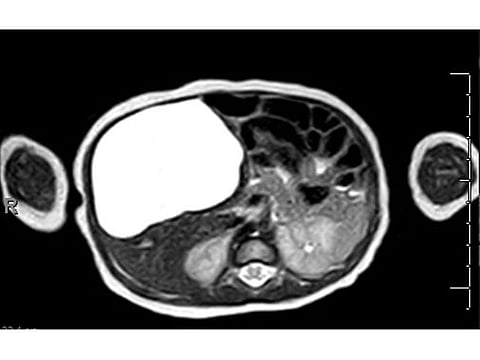

The couple took their newborn daughter to Dr Rajasekhar Cingapapu, a paediatric surgeon at Burjeel Medical City, who examined the baby and monitored her for two weeks. A detailed MRI scan revealed the size, position and the relation of the cyst to the surrounding vital organs. Based on those assessments, surgery was advised.

Dr Cingapapu said: “Giant congenital liver cysts are rare and difficult to diagnose clinically. The cyst may affect other organs or rupture. It may also cause an infection or internal bleeding to worsen the condition.”